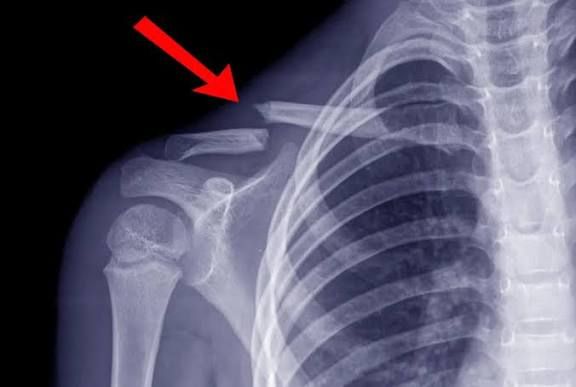

يبدأ التشخيص بفحص سريري يتبعه تصوير بالأشعة السينية لتحديد:

ـ مكان الكسر

ـ نوعه

ـ مدى انفصال الأجزاء

وفي الحالات المعقدة يستخدم الأطباء الأشعة المقطعية قبل وضع خطة العلاج.